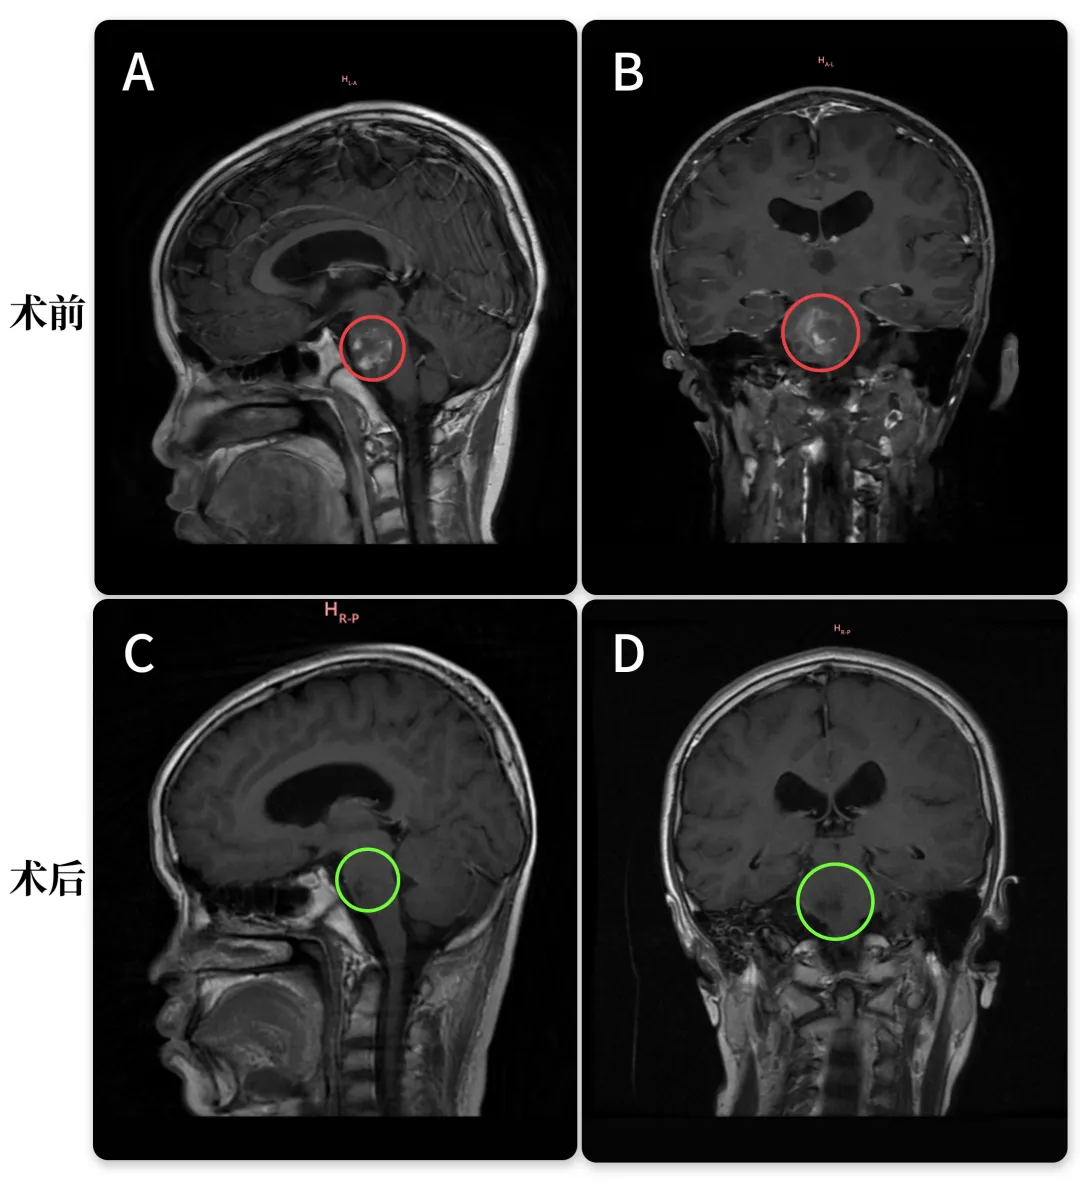

30岁男性—中脑顶盖胶质瘤

“我去了很多医院,也找了很多医生。但都告诉我,做手术的话,要么就是致残,致残率比较高,要么就是嘴歪眼斜的,生活质量不好。

对治疗结果相当满意,巴教授治疗后,我回到云南,去了医院复查,医生都说我这是一个奇迹。在他们看来是不可能完成的任务,但是巴特朗菲教授确实完成了。”